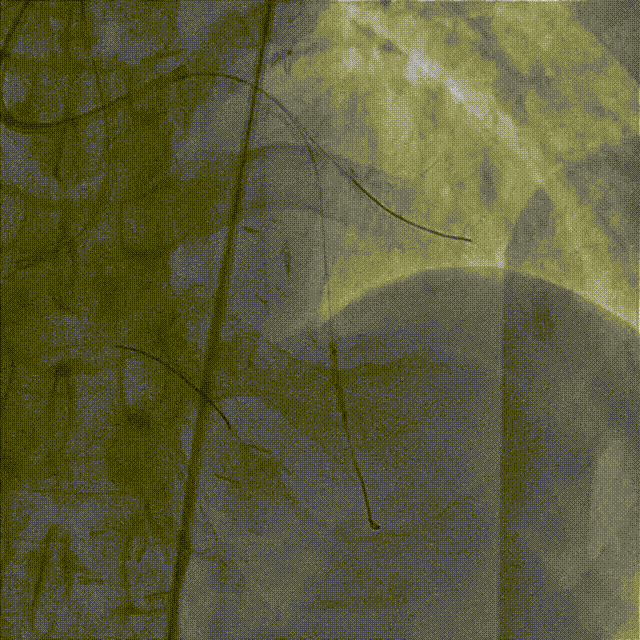

依次用Pinoeer 2.0mm x 15mm、Pinoeer 2.5mm x 15mm球囊至病变处反复扩张,送入Marvel导丝至D1远段做保护,LAD行IVUS检查。

IVUS检查示:可见导丝全程走行与血管真腔,近中段重度纤维增生斑块伴局部钙化,远段血管床废用性萎缩。

于LAD病变处由远及近依次植入XIENCE Alpine 2.5mm x 18mm和XIENCE Alpine 3.0mm x 23mm支架各一枚。